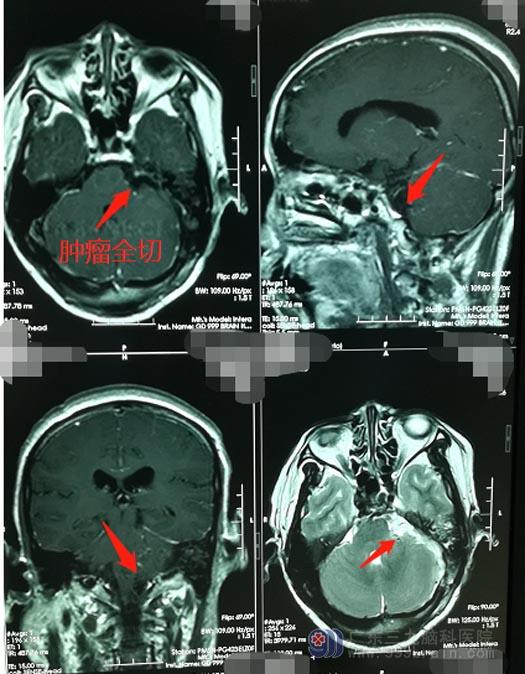

由于肿瘤与重要神经的特殊位置关系,手术中对神经、血管的保护就变得尤为重要。因桥小脑角区靠近脑干,此区域手术存在一定的风险,在医院副院长、神经外五科主任鲁明的耐心沟通下,陈大姐及家人都同意手术治疗。积极完善相关术前准备后,鲁明带领神经外五科医生团队为患者行“左侧听神经鞘瘤切除术”,术中见肿瘤压迫到听神经、三叉神经及舌咽神经,显微镜下仔细分离后都完整保留了下来,手术过程非常顺利。

术后的陈大姐没有出现面瘫、嘴角歪斜、面部麻木等后遗症,左侧的耳鸣及面部麻木的症状也得到明显的改善。